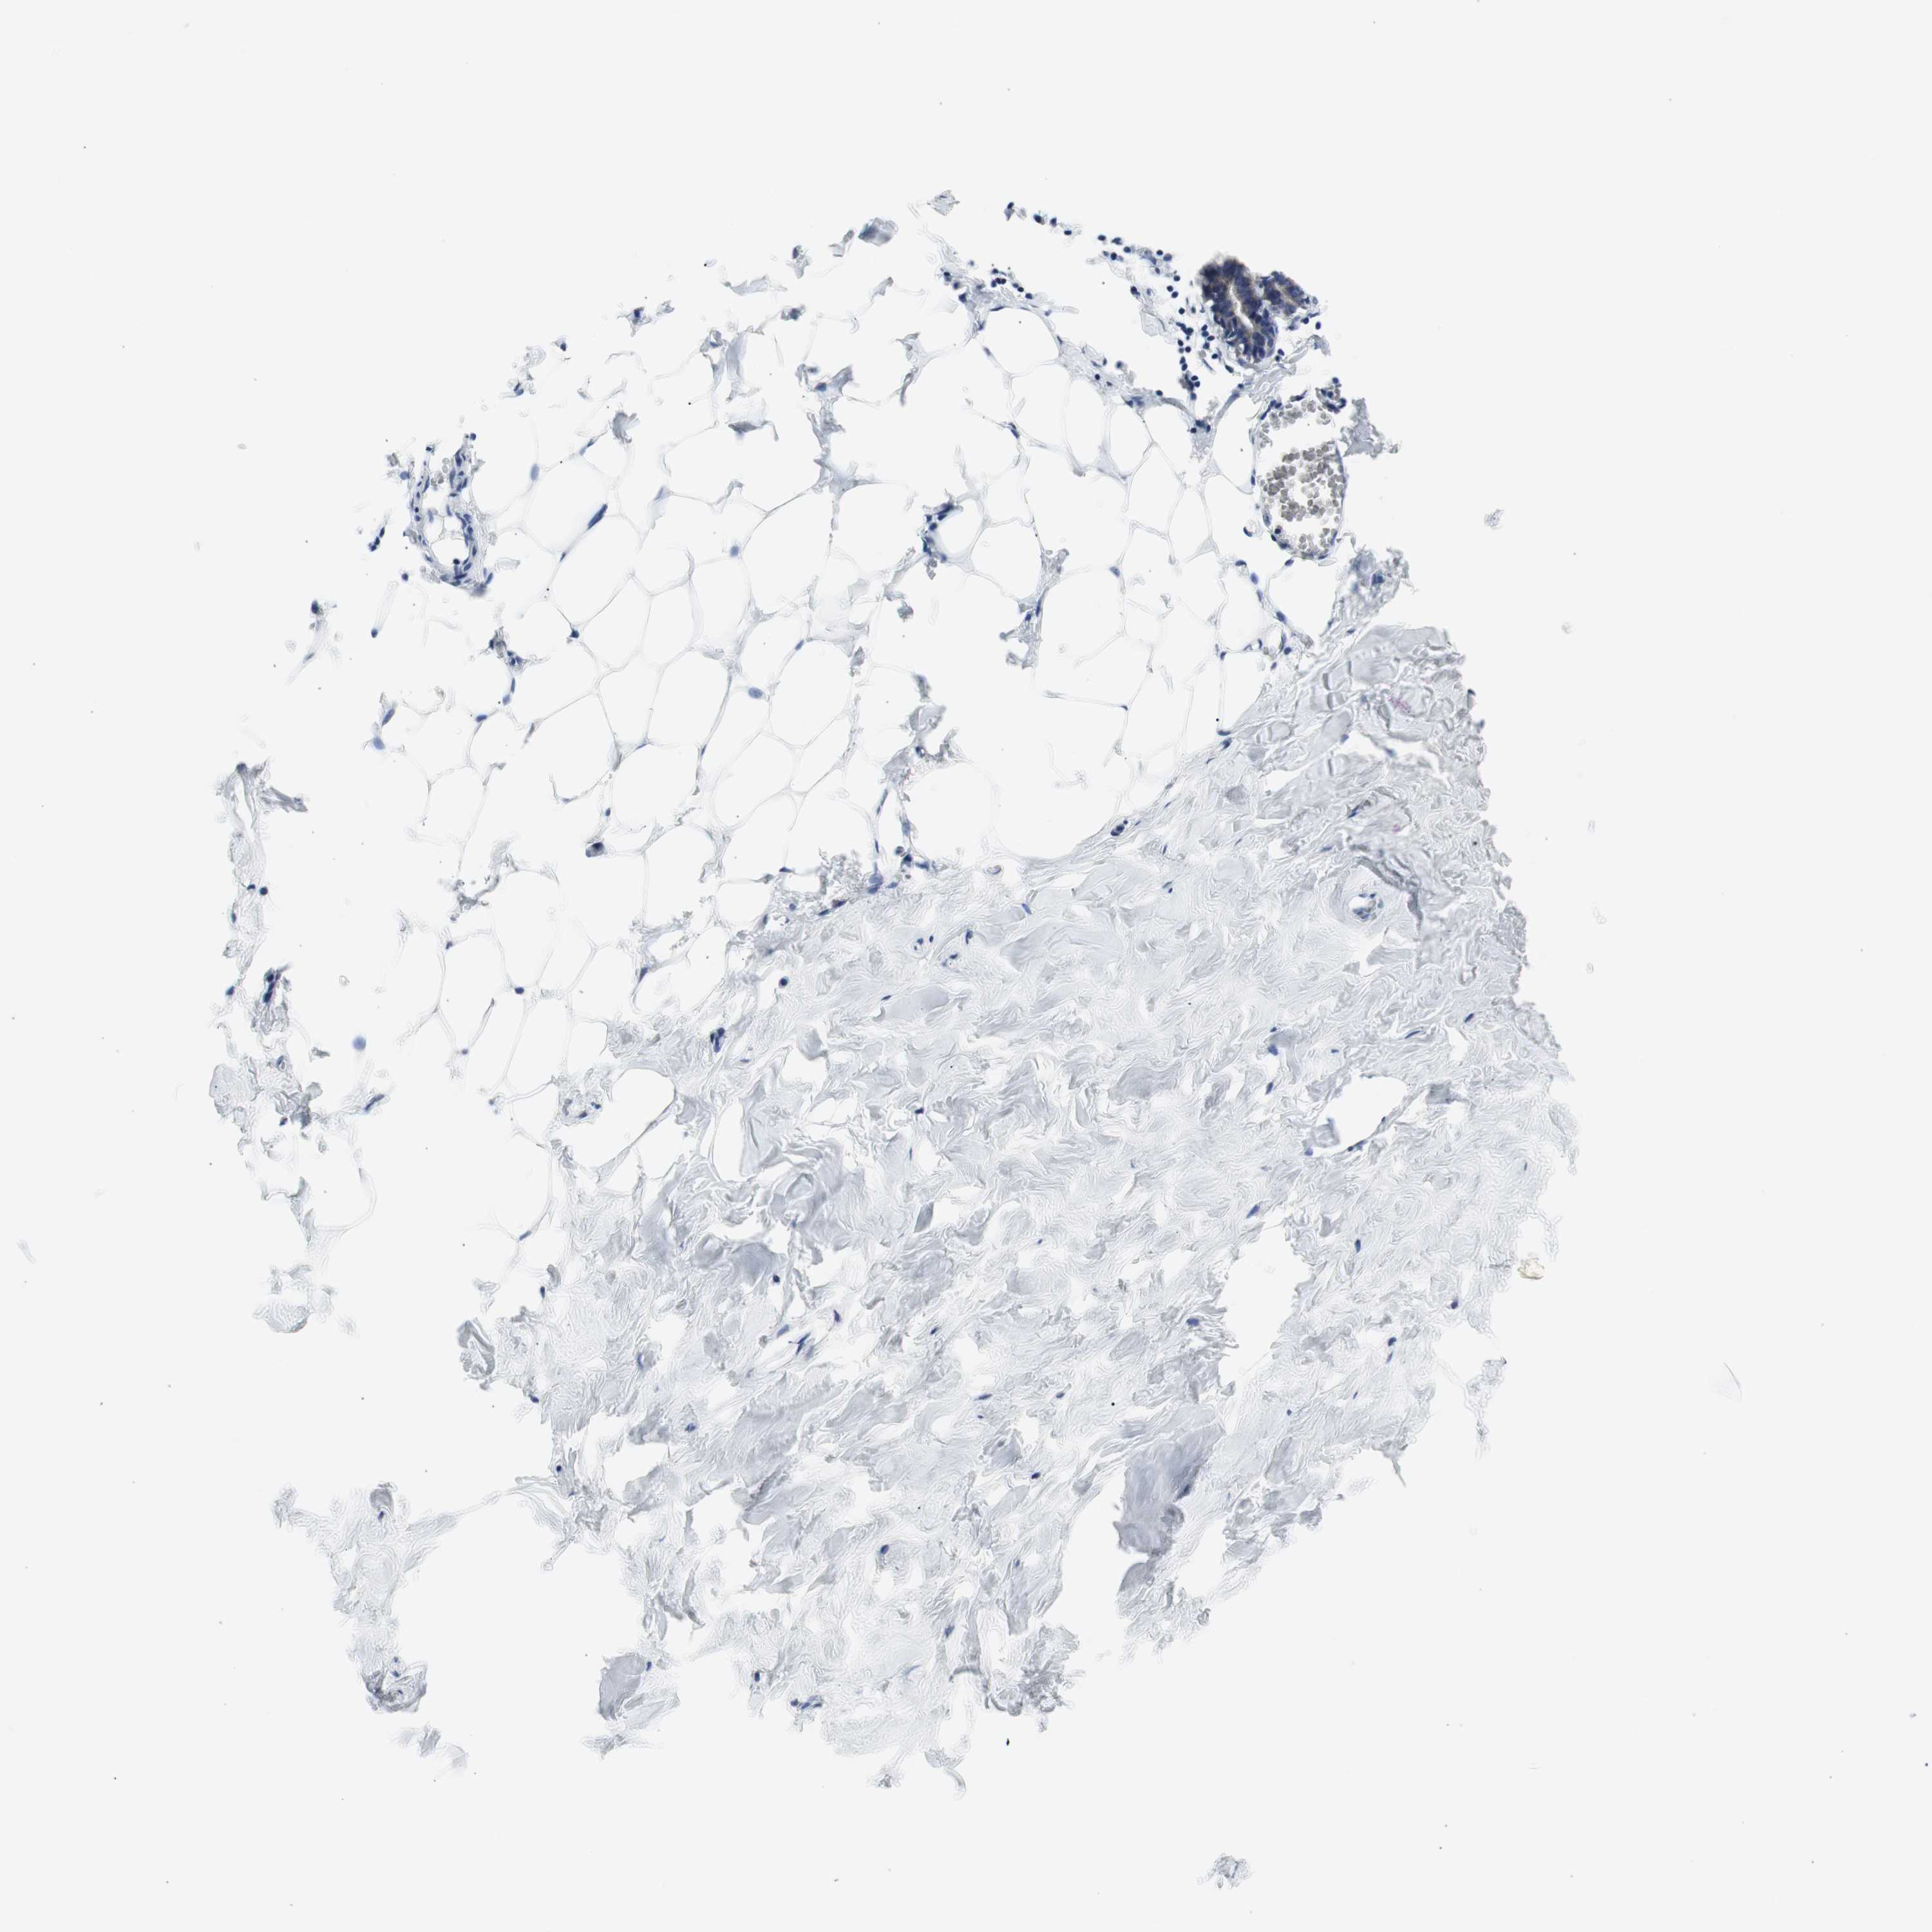

Antibody staining in the annotated cell types in the current human tissue is reported as not detected, low, medium, or high. This score is based on the staining intensity and fraction of stained cells.

Information about each individual sample is listed below, including gender, age, a tissue section image and estimated fractions of cell types. pTPM (transcripts per million) values give a quantification of the gene abundance which is comparable between different genes and samples.

Glandular cells: 40 Adipocytes: 5 Other cell types: 55